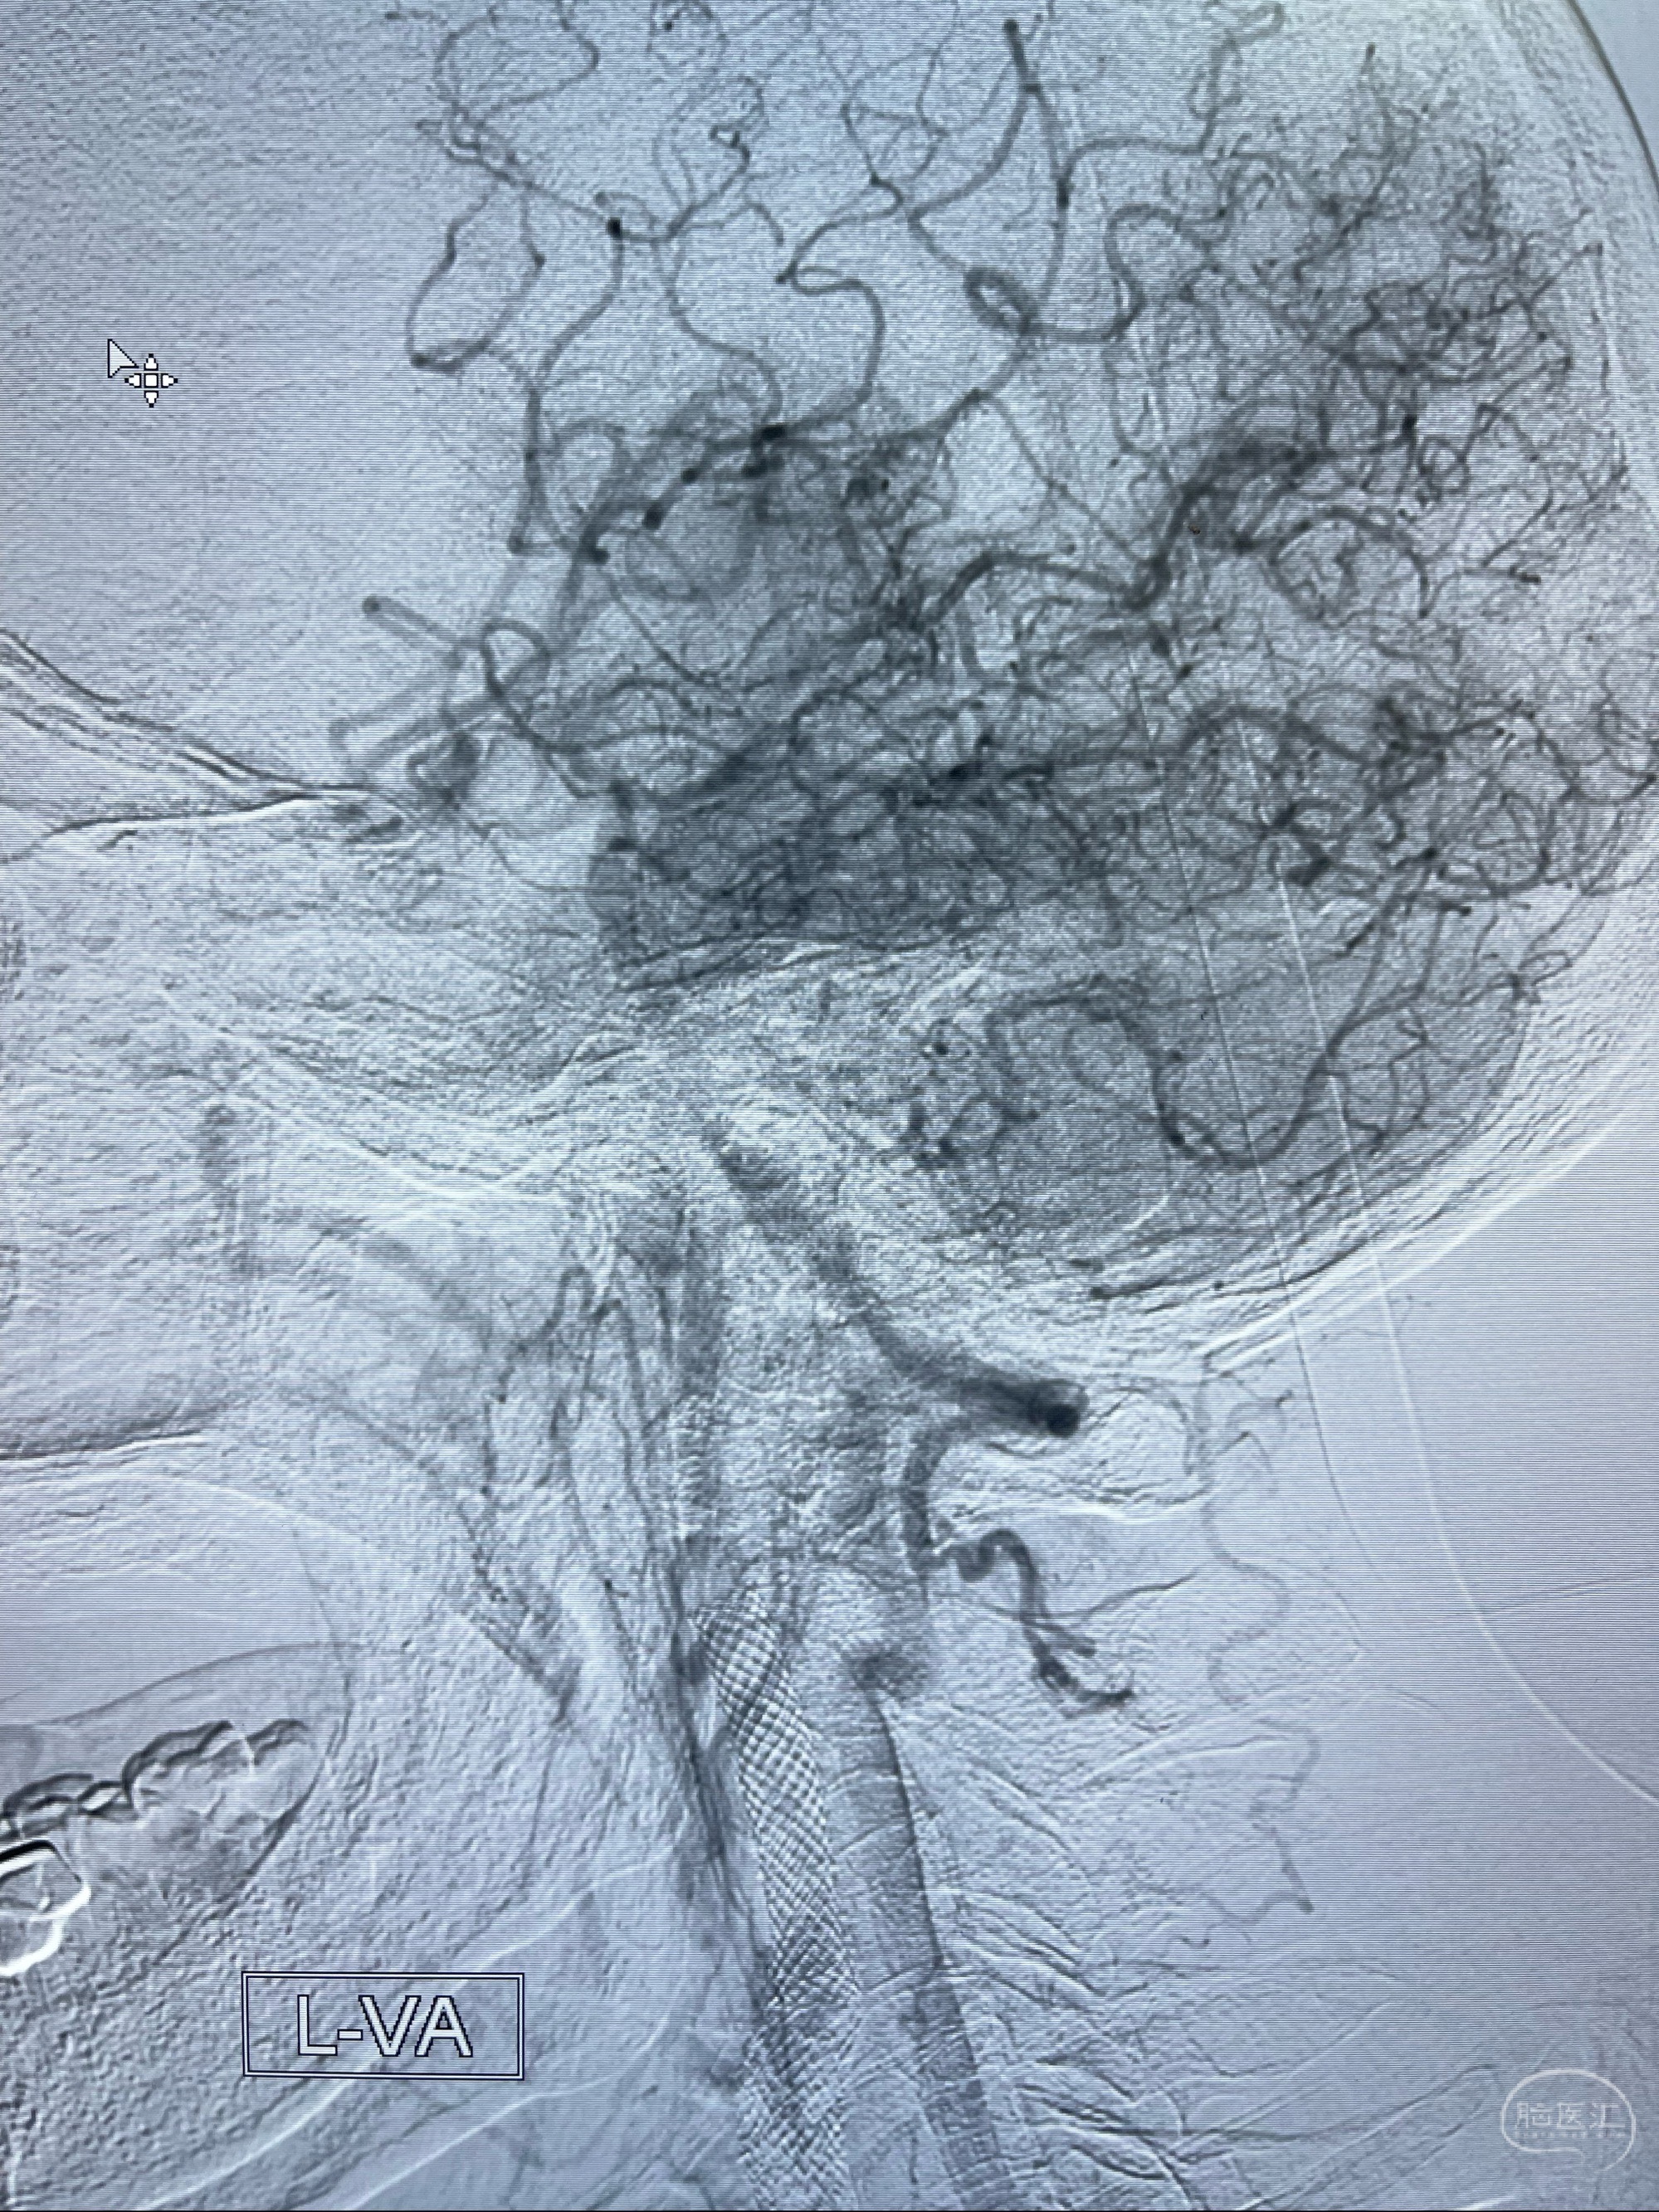

2023-07-10DSA:右侧颈内动脉岩骨段夹层伴中偏重度狭窄改变,左侧颈总动脉闭塞、右侧颈外动脉由右侧肋颈干甲颈干吻合代偿

左侧颈总动脉起始段至分叉部闭塞,起始部呈现子弹头样改变

左侧椎动脉可见代偿显示左侧前循环